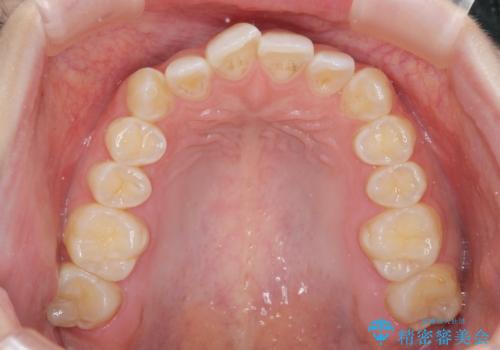

前歯のねじれを治したい マウスピース矯正治療

- 前歯のねじれを改善し、きれいな歯並びにしたい!と矯正治療を希望され来院されました。

マウスピース矯正システム、インビザラインのシミュレーションを用いて最終的な歯の位置をしっかりと確認したのち、きれいな歯並びとなるようマウスピース矯正治療を開始します。

ねじれとともに突き出たように見えていた前歯も見た目が大きく改善し、喜んでいただくことができました。